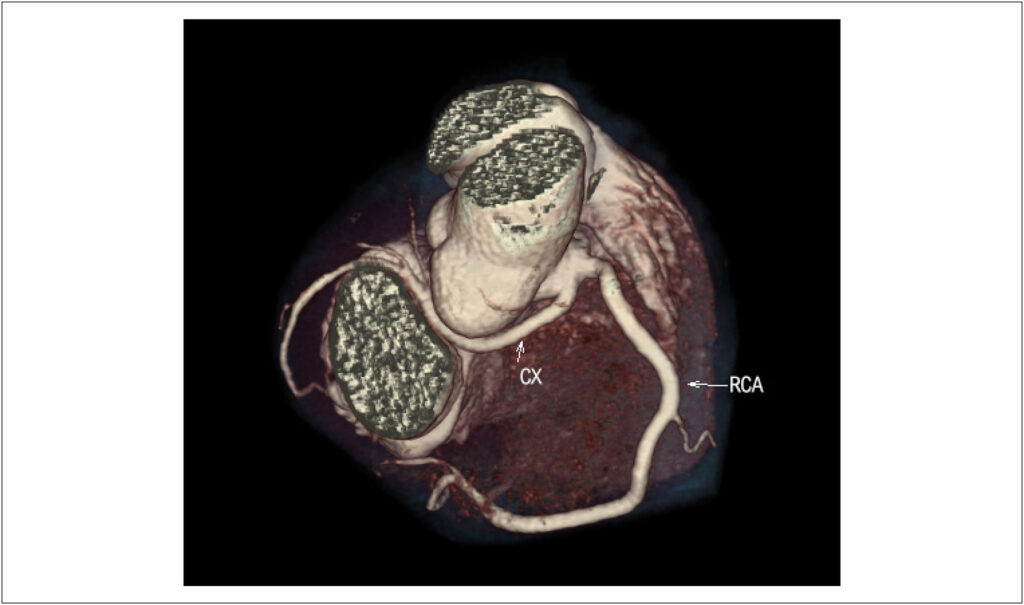

Anomalous Origin of the Coronary Artery from an Inappropriate Coronary Sinus

Congenital anomaly of the coronary arteries is a potentially lethal disease, especially in young people. Currently, non-invasive cardiovascular imaging tests have shown better definition of the origin and course of the coronary arteries. Surgical treatment should be indicated in symptomatic patients, while the ideal management of asymptomatic patients remains controversial. We report a case of anomalous origin of the left coronary artery from the right coronary sinus with an interarterial course, in an asymptomatic patient treated with revascularization surgery.